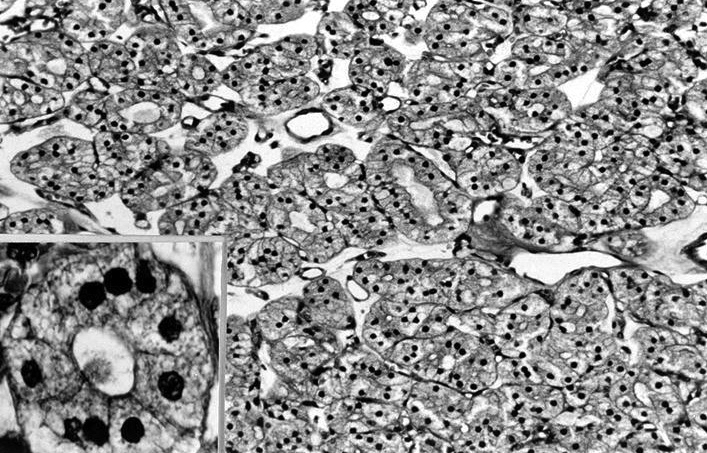

Electron microscopy description

- Similar to normal thyroid gland and hyperplastic nodules

- Hyperfunctioning follicular adenomas: organelle rich cytoplasm, especially rough endoplasmic reticulum; numerous, long microvilli on surface (Am J Clin Pathol 1982;78:299)

- Clear cell follicular adenomas: cytoplasmic vesicles of variable size; these may be dilated cisternae of the rough endoplasmic reticulum or mitochondria, lysosomes or endocytic vesicles (Virchows Arch A Pathol Anat Histol 1978;380:205)

Electron microscopy images